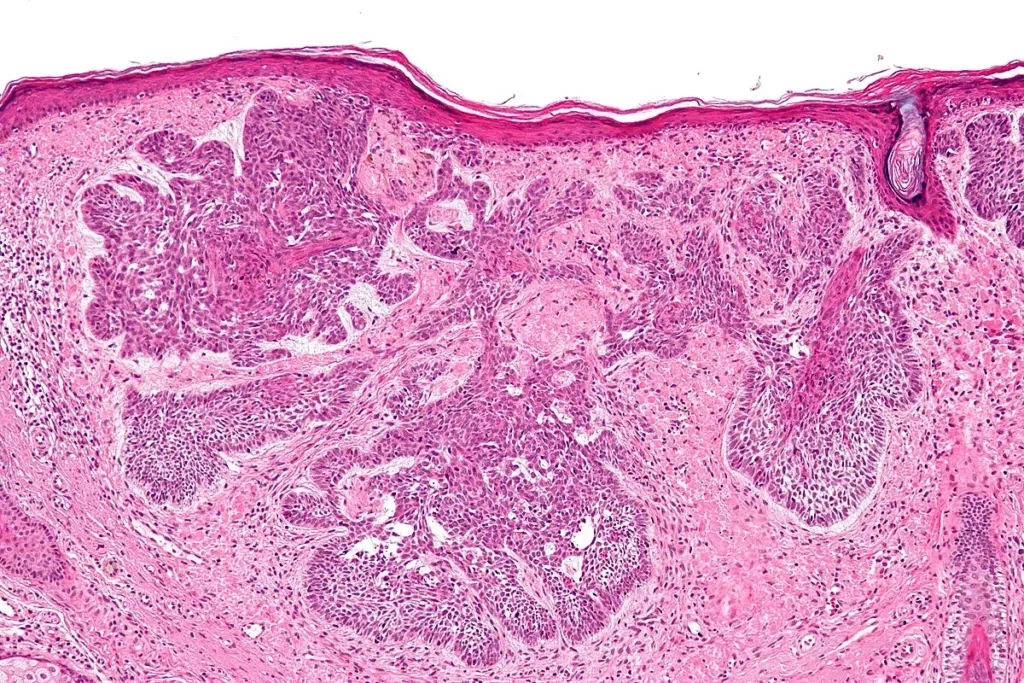

In the modern era, the diagnosis of sarcoma relies heavily on molecular pathology. Because many sarcomas appear similar under the microscope (spindle cells or small, round, blue cells), traditional histology is often insufficient. Fluorescence In Situ Hybridization (FISH) and Reverse Transcription Polymerase Chain Reaction (RT-PCR) are used to detect the specific chromosomal translocations that define many sarcoma subtypes. For example, detecting the EWSR1 gene rearrangement confirms Ewing Sarcoma, while the SYT-SSX fusion confirms Synovial Sarcoma. Next-Generation Sequencing (NGS) panels are increasingly used to identify rare mutations or fusion partners in “undifferentiated” sarcomas, potentially revealing targets for personalized therapy.

Sarcoma staging follows the TNM (Tumor, Node, Metastasis) system but places a unique and significant emphasis on Grade (G). The histological grade—determined by the degree of cellular differentiation, mitotic rate (speed of division), and the amount of tumor necrosis—is the most powerful predictor of metastasis and survival.

• The Differentiation Score assesses how closely the tumor resembles normal adult tissue, with lower scores indicating better differentiation.

• Mitotic Count quantifies the number of dividing cells per high-power field, reflecting the tumor’s proliferative rate.

• Tumor Necrosis measures the percentage of dead tissue within the tumor mass, a marker of rapid growth outstripping blood supply.

• The FNCLCC Grading System combines differentiation, mitotic count, and necrosis to assign a Grade 1, 2, or 3.

• Ki-67 Proliferation Index is an immunohistochemical marker used to assess the fraction of actively cycling cells.